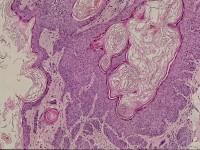

![Pilar sheet acanthoma (click on photo to enlarge) [source: www.huidziekten.nl] Pilar sheet acanthoma](../../../images/pilar-sheath-acanthoma-1z.jpg) |

| pilar

sheet acanthoma |